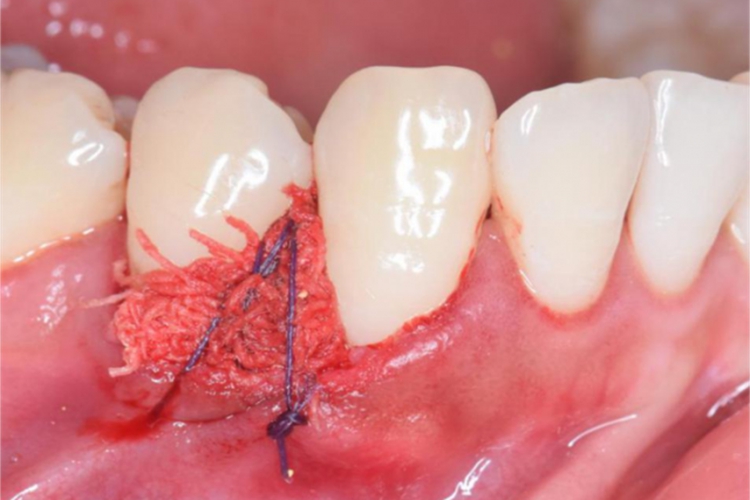

缝合创面:切除后创面可利用颊或腭(舌)侧黏膜滑行覆盖创面;若不能闭合时,可用碘仿纱条覆盖创面,缝合固定,或用牙周塞治剂覆盖创面。